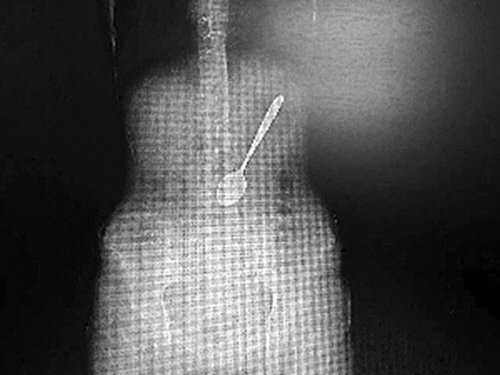

Chiếc muỗng mà người phụ nữ nuốt phải

Lúc đầu các bác sĩ chưa tin lời kể của nạn nhân nhưng ảnh chụp X-quang cho thấy rõ chiếc muỗng dài hơn 15cm trong bụng.

Bằng cách chụp X-quang, bác sĩ phát hiện ra chiếc muỗng dài hơn 15cm trong bụng cô Wang, nằm chếch một góc 30 độ.

Chiếc muỗng nằm chếch một góc 30 độ trong bụng của nạn nhân